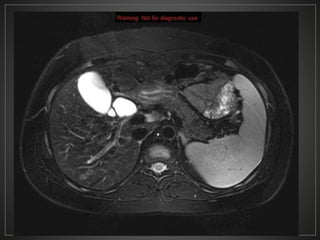

CPRE: Dilataciones saculares de CBIH. TC: Simple:Áreas redondas, hipointensas en topografía de CBIH. Contraste: Signo del punteado central. RM: T2: Espacios quísticos hiperdensos

• #41 Adquisicion axial de R.M. ponderada en T2 con supresion grasa, donde se observa una imagen de morfologia ovalda, de bordes definidos, hiperintensa, en topografia de coledoco, en relacion a quiste de coledoco.